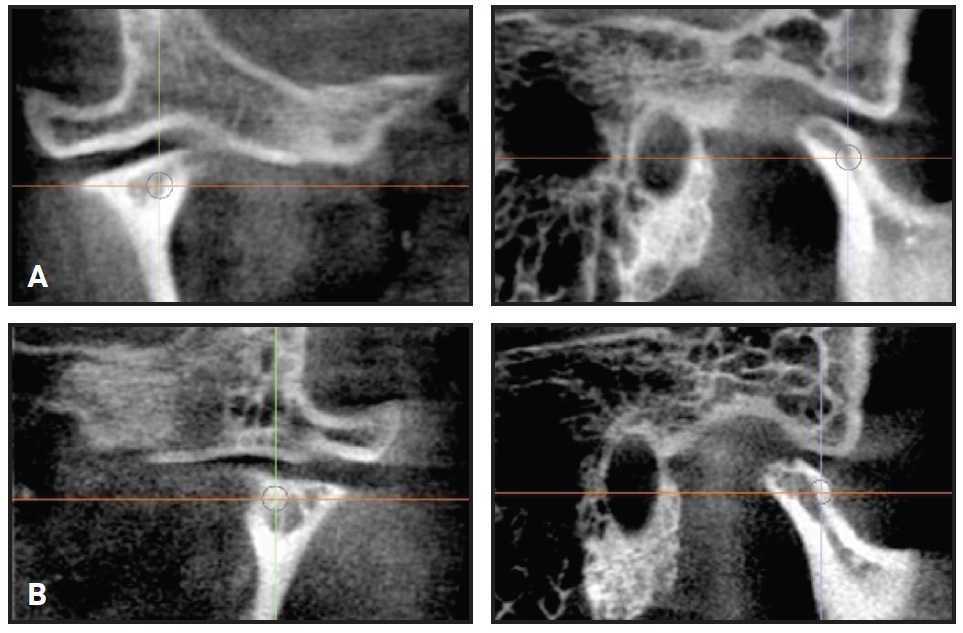

Post-treatment dental cast measurements of the WALA ridge were increased by 5mm at the mandibular canines and 2.5mm at the first premolars10 (Fig. 6).

Fig. 6 A. WALA ridge10 before treatment. B. After treatment.

This arch expansion was obtained not only by lateral tooth movement, which increased the intercanine, interpremolar, and intermolar widths, but also by alveolar bone remodeling following movement of the teeth.9

Post-treatment computed tomographic (CT) images confirmed that the integrity of the alveolar bone and the dental roots was maintained (Fig. 7).

Fig. 7 Preservation of alveolar bone tissue and dental roots after treatment.

The lower central incisors showed the greatest alveolar bone loss, but the damage was minimal. Unfortunately, a CT scan was not required before orthodontic treatment, and therefore it is not possible to determine whether this bone loss was preexistent or caused by orthodontic tooth movement. In any event, the overall results were excellent, and the cost-benefit return of the orthodontic treatment was unquestionable.